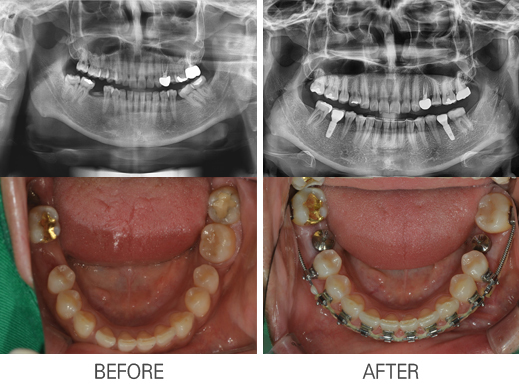

±³Á¤À» µ¿¹ÝÇÑ ÀÓÇöõÆ®

: ±³Á¤À» µ¿¹ÝÇÑ ÀÓÇöõÆ®